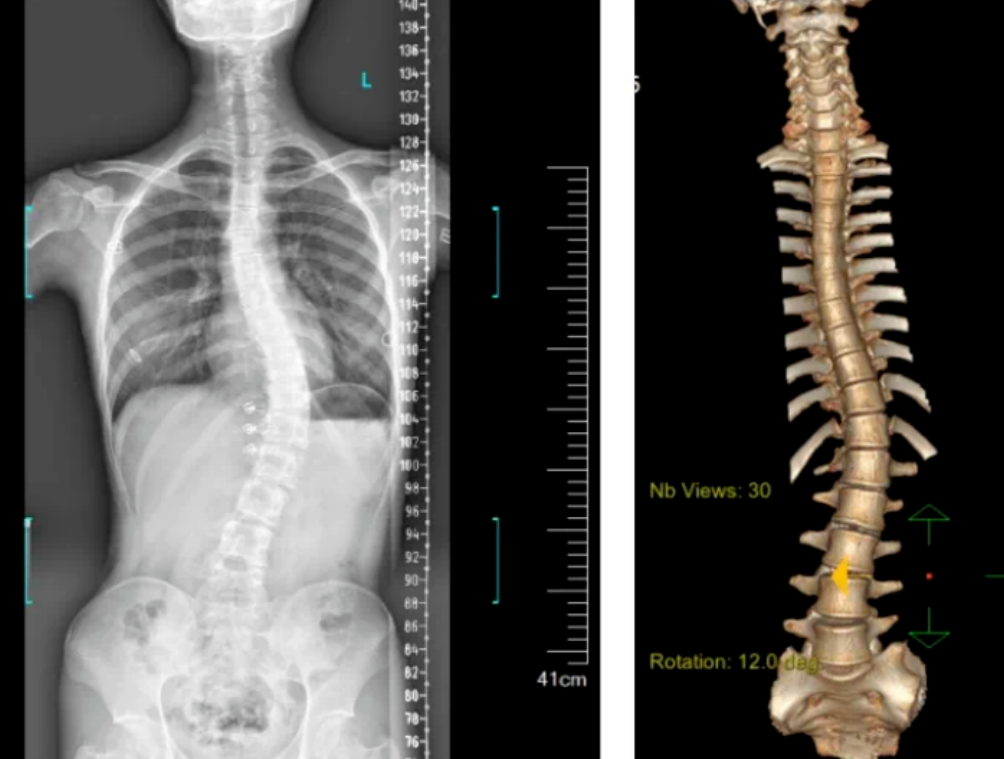

3D機(jī)器視覺(jué)的脊柱檢測(cè)圖

3D視覺(jué)技術(shù)可以用于自動(dòng)化的脊柱側(cè)彎?rùn)z測(cè)。通過(guò)使用3D成像設(shè)備,如結(jié)構(gòu)光或激光掃描儀,機(jī)器人可以快速捕捉老年人的脊柱圖像,并利用機(jī)器視覺(jué)算法分析脊柱的形態(tài)和角度,從而判斷是否存在側(cè)彎現(xiàn)象。

基于顯揚(yáng)科技HY-HY-X3 3D機(jī)器視覺(jué)的脊柱側(cè)彎?rùn)z測(cè)系統(tǒng),能夠在無(wú)需接觸患者的情況下,快速獲取患者脊柱的三維圖像。該系統(tǒng)使用高精度的3D攝像頭,通過(guò)結(jié)構(gòu)光或激光掃描技術(shù),捕捉到脊柱的詳細(xì)形態(tài)。

系統(tǒng)掃描速度為15Hz,精度達(dá)到±0.01mm,結(jié)合自研智能算法,能夠進(jìn)行全彩信息學(xué)習(xí),還能通過(guò)深度攝像頭捕捉人體背部的形態(tài)變化,轉(zhuǎn)化為對(duì)應(yīng)的脊柱形態(tài),并計(jì)算脊柱的彎曲角度,從而了解患者的側(cè)彎程度。這種方法避免了傳統(tǒng)X光片檢測(cè)帶來(lái)的輻射風(fēng)險(xiǎn),實(shí)現(xiàn)了無(wú)輻射、快速、便捷的篩查。

針對(duì)老年人常見(jiàn)的慢性病和疼痛等問(wèn)題。BFT平臺(tái)中的顯揚(yáng)科技開(kāi)發(fā)的3D機(jī)器視覺(jué)系統(tǒng),可以對(duì)患者的脊柱進(jìn)行三維空間內(nèi)的精準(zhǔn)定位與測(cè)量。通過(guò)立體視覺(jué)技術(shù),系統(tǒng)能夠獲取脊柱的精確三維坐標(biāo)信息,為脊柱側(cè)彎的檢測(cè)提供數(shù)據(jù)支持,可以更直觀了解脊柱的形態(tài)和側(cè)彎程度,從而進(jìn)行準(zhǔn)確的診斷。